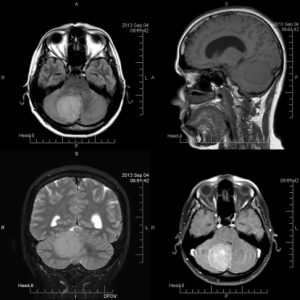

A cancer diagnosis is one of the worst pieces of news you could get. Nearly every organ in the human body can succumb to cancer cells that not only limit function but can also lead to death. Glioblastoma is a tumor that occurs in the brain and spinal cord and can be life-threatening, depending on the location and rate of growth. However, according to a new study, glioblastoma patients may benefit from a vaccine-chemotherapy combination, improving overall survival.

A cancer diagnosis is one of the worst pieces of news you could get. Nearly every organ in the human body can succumb to cancer cells that not only limit function but can also lead to death. Glioblastoma is a tumor that occurs in the brain and spinal cord and can be life-threatening, depending on the location and rate of growth. However, according to a new study, glioblastoma patients may benefit from a vaccine-chemotherapy combination, improving overall survival.

Glioblastoma is considered the most aggressive type of cancer that begins in the brain and its exact cause is still unclear. Risk factors include various genetic disorders or even a previous history of radiation therapy. Currently, there is no clear method of preventing the disease, and despite therapy, it has a high incidence of recurrence. The most common length of survival following a diagnosis is about 12 to 15 months, with less than 3 to 5 percent of those affected surviving longer than five years. The symptoms of brain cancer can present in multiple ways and are initially non-specific, making it possible to miss the diagnosis early on. The following are such symptoms: